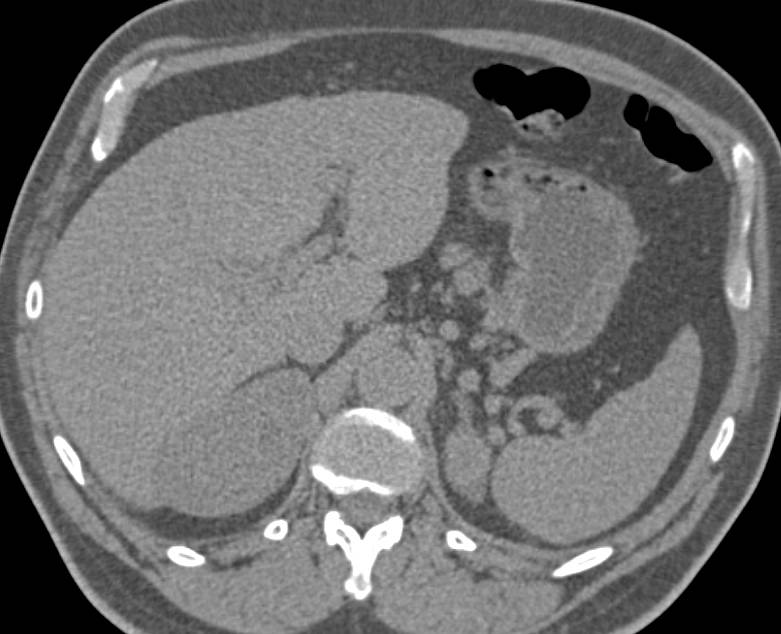

Polycystic Liver and Polycystic Renal Disease